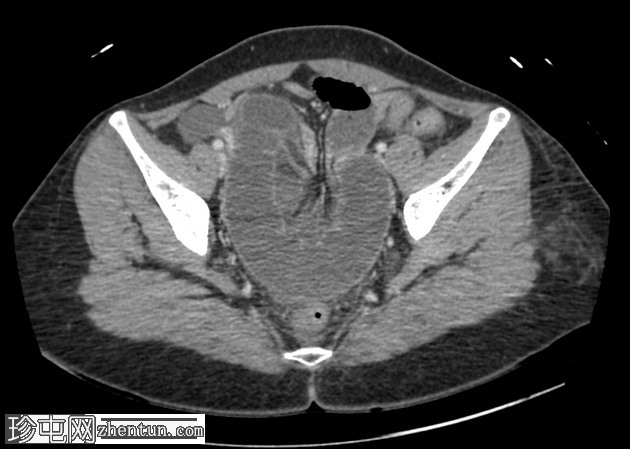

轴位增强扫描(门静脉期)

小肠袢明显扩张,左侧附件区可见双移行点,远端回肠短段闭袢梗阻,肠颈位于左侧输卵管/左侧子宫血管附近。

肠系膜血管充血,腹盆腔可见游离液体,提示肠系膜充血。

远端回肠袢和结肠已减压。

无肠缺血或穿孔的影像学证据。

CT 检查结果提示左侧附件水平小肠短段闭袢性梗阻。肠段的移行点和形态提示可能存在阔韧带或与左侧附件结构相关的粘连带引起的内疝。